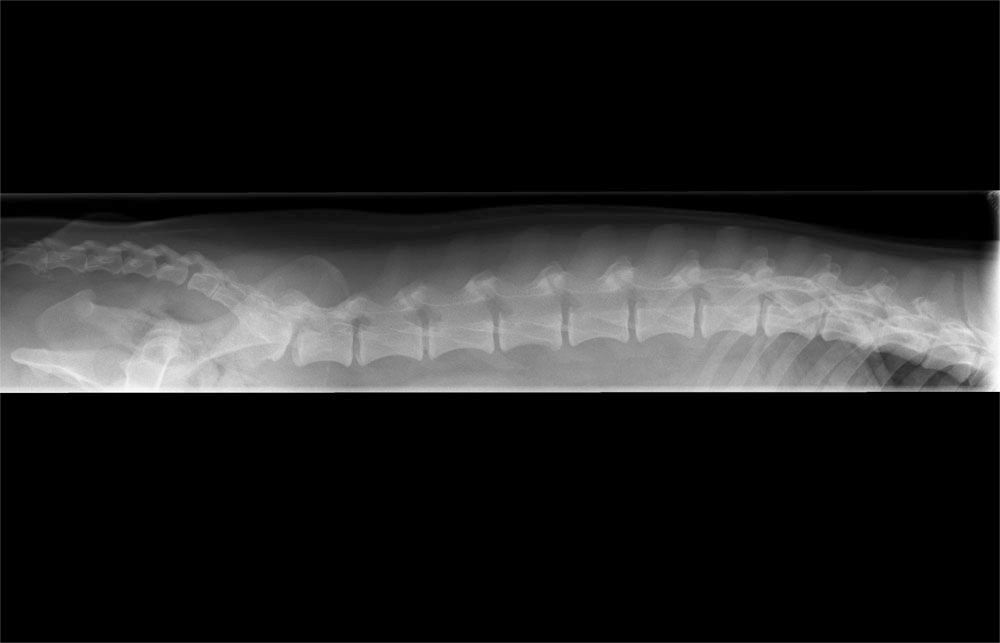

Foto's van de rug zijn niet alleen erg moeilijk om te maken omdat het recht liggen van de wervels bij het wakkere dier moeilijk, zo niet onmogelijk, is; je kan enkel iets zeggen over de botten. Druk op de zenuwen door bv een hernia kan je normaliter niet zien op een foto. Dus je kan niet zeggen dat de rug in orde is enkel op basis van foto's. Ik zou teruggaan naar de specialist.

Klopt, zei DA ook. Dat foto's een hernia niet uitsluiten.Anne&Taar schreef:foto's van de rug zijn niet alleen erg moeilijk om te maken omdat het recht liggen van de wervels bij het wakkere dier moeilijk, zo niet onmogelijk, is; je kan enkel iets zeggen over de botten. Druk op de zenuwen door bv een hernia kan je normaliter niet zien op een foto. Dus je kan niet zeggen dat de rug in orde is enkel op basis van foto's. Ik zou teruggaan naar de specialist.